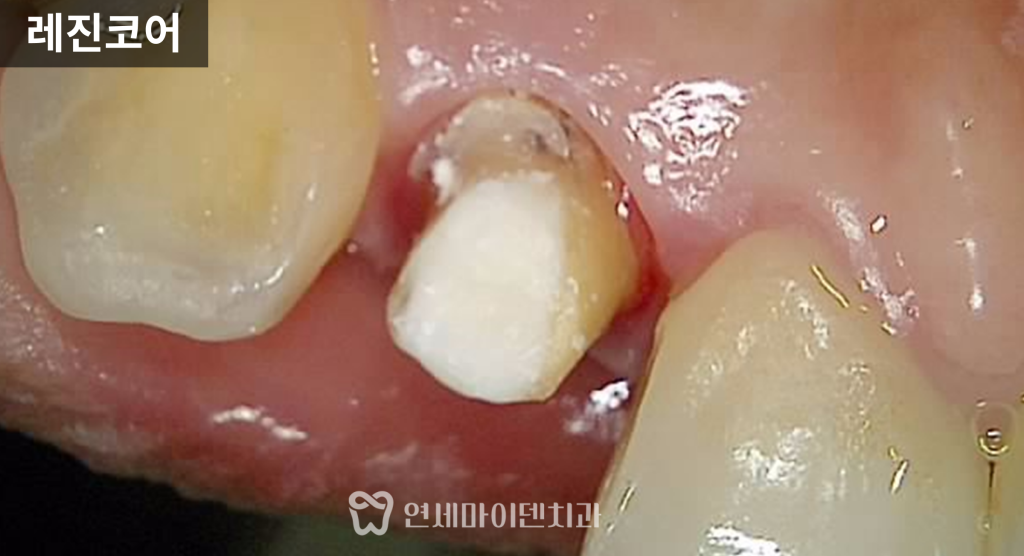

치료 후에는 임시치아 상태

일상생활을 하며 경과를 확인했고,

통증과 불편감이 사라진 것을 확인한 뒤

레진 코어를 통해 내부 구조를 보강하고

최종 보철까지 진행했습니다.